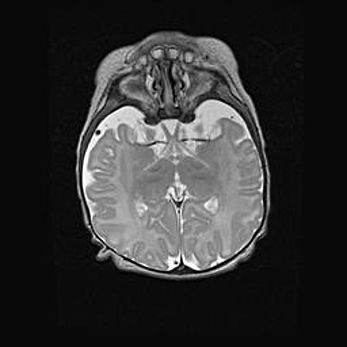

Церебральная ишемия II.

Возраст: 5 дней

Вес: 3400 г

Пол: женский

Окружность головы: 35 см

Срок гестации: 39 недель

Церебральная ишемия – это заболевание, характеризующееся недостаточностью (гипоксией) либо полным прекращением (аноксией) снабжения мозга кислородом по причине закупорки одного или нескольких сосудов. Это приводит к  что метаболическим расстройствам различной степени тяжести в тканях головного мозга, развитию коагуляционных некрозов и гибели нейронов.